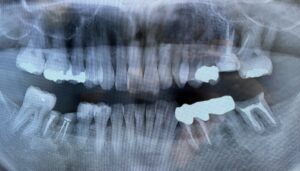

痛みや不快感の原因をチェックする

根管治療を始める前に、まずは痛みや不快感の原因をチェックが行われます。歯科用レントゲン写真の撮影で、目視では確認できない部分まで精密に検査をします。

状況によってはCTスキャンなどを用いて確認し、根管治療が必要であると判断されれば治療が開始されます。